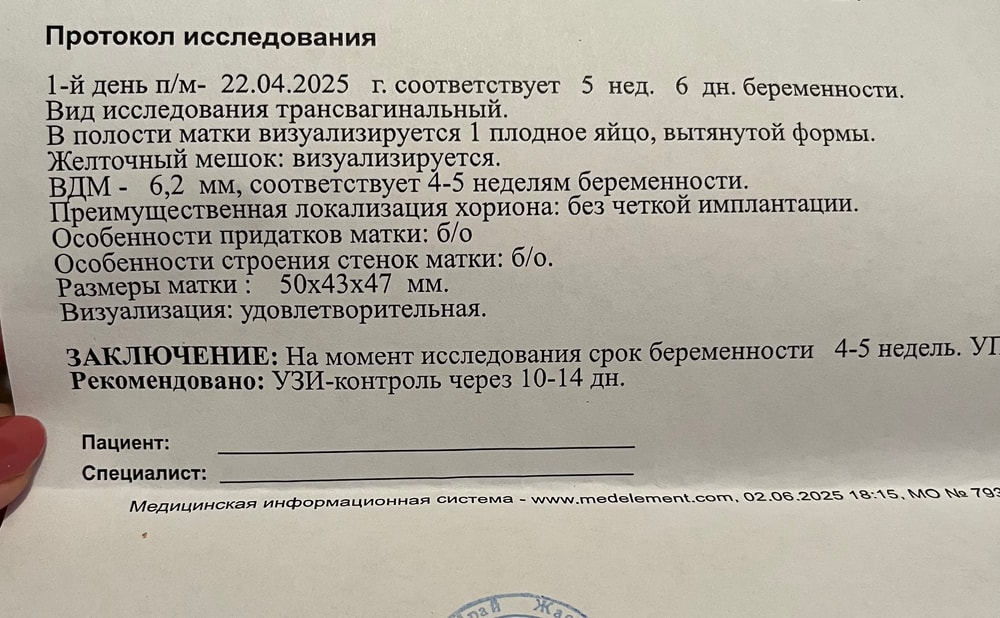

Пя 6,2 мм у вас,это буквально 3 недели от овуляции и 5 акушерских,если овуляция на 20 д.ц была,то УЗИ соответствует сроку

Z G, тогда поздняя овуляция исключена,тесты первые полоски начинают выдавать в среднем на 10 дпо,если у вас полоски были на 24 д.ц уже,то овуляция была на 14 д.ц,т.е нормальная,с поздней они бы намного позже показали,тогда к сожалению УЗИ совсем не соответствует сроку,в 6 недель с нормальной овуляцией и пя больше должно быть и желточный мешочек и зачатки эмбриона уже

Овуляция поздняя была? Фактический срок на неделю меньше, чем по месячным.

Z G, если у вас цикл 28-30 дней и овуляция была на 14-15, картина не очень хорошая. Если же она могла на недельку опоздать, то всё в порядке, дней через 10 может идти повторно и слушать сердечко.

По узи вам сказали, что вы беременны :))))

Сейчас следить за доровьем и ждать 1 скрининга. Для себя можно сделать УЗИ ещё через месяц, там и локализация уже будет видна.

Меня б смутило, что в таком маленьком ПЯ уже хорошенький ЖМ. Смотрите в динамике 🙏🏽